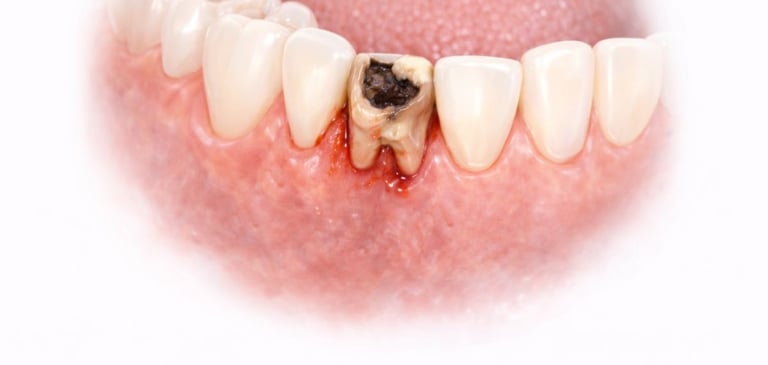

When Is Tooth Extraction Needed?

Tooth extraction may be recommended in cases of:

Severe tooth decay or infection

Broken or fractured tooth beyond repair

All images shown here represent real clinical cases of teeth extractions done at our dental clinic with patient consent.

Illustrative images and similar real clinical cases requiring tooth extraction